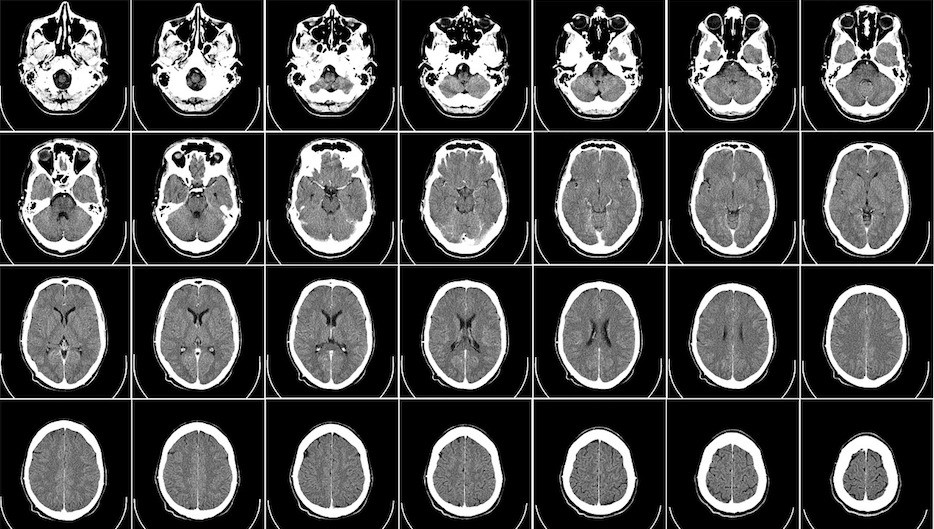

47 yaşlı kişi baş beyin qan dövranı pozğunluğu əlamətləri ilə Moskva əyaləti xəstəxanasına gətirilir.

Nevroloq A. Burnyazina bildirib ki, MRT çəkimindən sonra pasiyentin sol beyin yarımkürəsinin olmaması aşkarlandı.

Medicina.az xəbər verir ki, həkimlər kişinin ömrü boyu yalnız beyninin fəaiyyətdə olan yarisi ilə yaşayıb.

Vəziyyəti yaxşılaşandan sonra pasiyent dəqin müayinə və müalicələrdən imtina edərək evinə gedib. O, hesab edir ki, ona müdaxilə etmək olmaz. "Mən bu yarım beynimlə aliməktəbə daxil olmuşam, əsgərlikdə olmuşam, 2 uşaq atasıyam, mühəndisəm, bundan sonra mənə problem lazım deyil. Məni sağlamlığımda heç nə narahat etmir”.

Nevroloqun sözlərinə görə belə faktlar tibdə çox nadir halda rast gəlinir və yarımkürənin birinin inkişafdan qalması hələ embrion dövründə başlayıb.